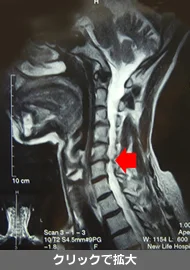

MRIを撮影しましょう

首の椎間板、胸の椎間板、腰の椎間板に異常があると、首の一部分のみの動きが大きくなり、むち打ち症を悪化させます。

首の椎間板変性

首の骨に椎間板の薄い部分があると、その部分のぐらつきが多くなり、むち打ち症が長引きます。

椎間板変性があっても、健康な背骨の部分の動きを取り戻し、変性部分の運動を代行できるようになれば、十分な回復が望めます。MRIで異常のない場合は、まずは不安と心配を解決しましょう。